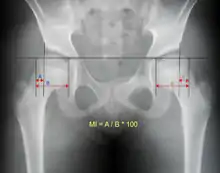

An anterior-posterior (AP) X-ray of the pelvis and a cross-table lateral X-ray[24] of the effected hip are ordered for diagnosis.[4][5][16] The size of the head of the femur is then compared across both sides of the pelvis. The affected femoral head will appear larger if the dislocation is anterior, and smaller if posterior.[7] A CT scan may also be ordered to clarify the fracture pattern.[19]